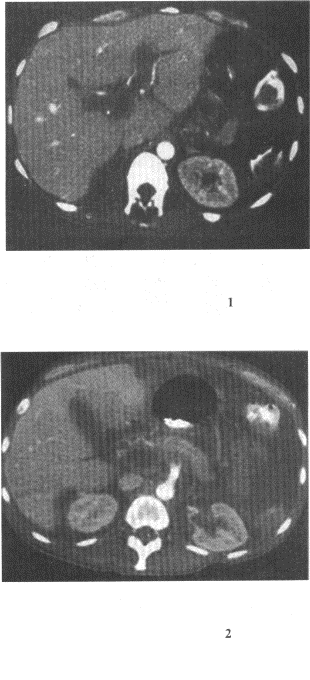

患者30歲,女性,右上腹持續性痛,腹脹,胸悶,食欲減退,消瘦。實驗室檢查,甲胎蛋白血清AFP試驗陽性血清堿性磷酸酶(ALP)增高,CT示肝右前葉病灶。

17.分析圖像,結合病史,最可能的診斷是

正確答案:17.C;18.A;19.D;20.C;21.E